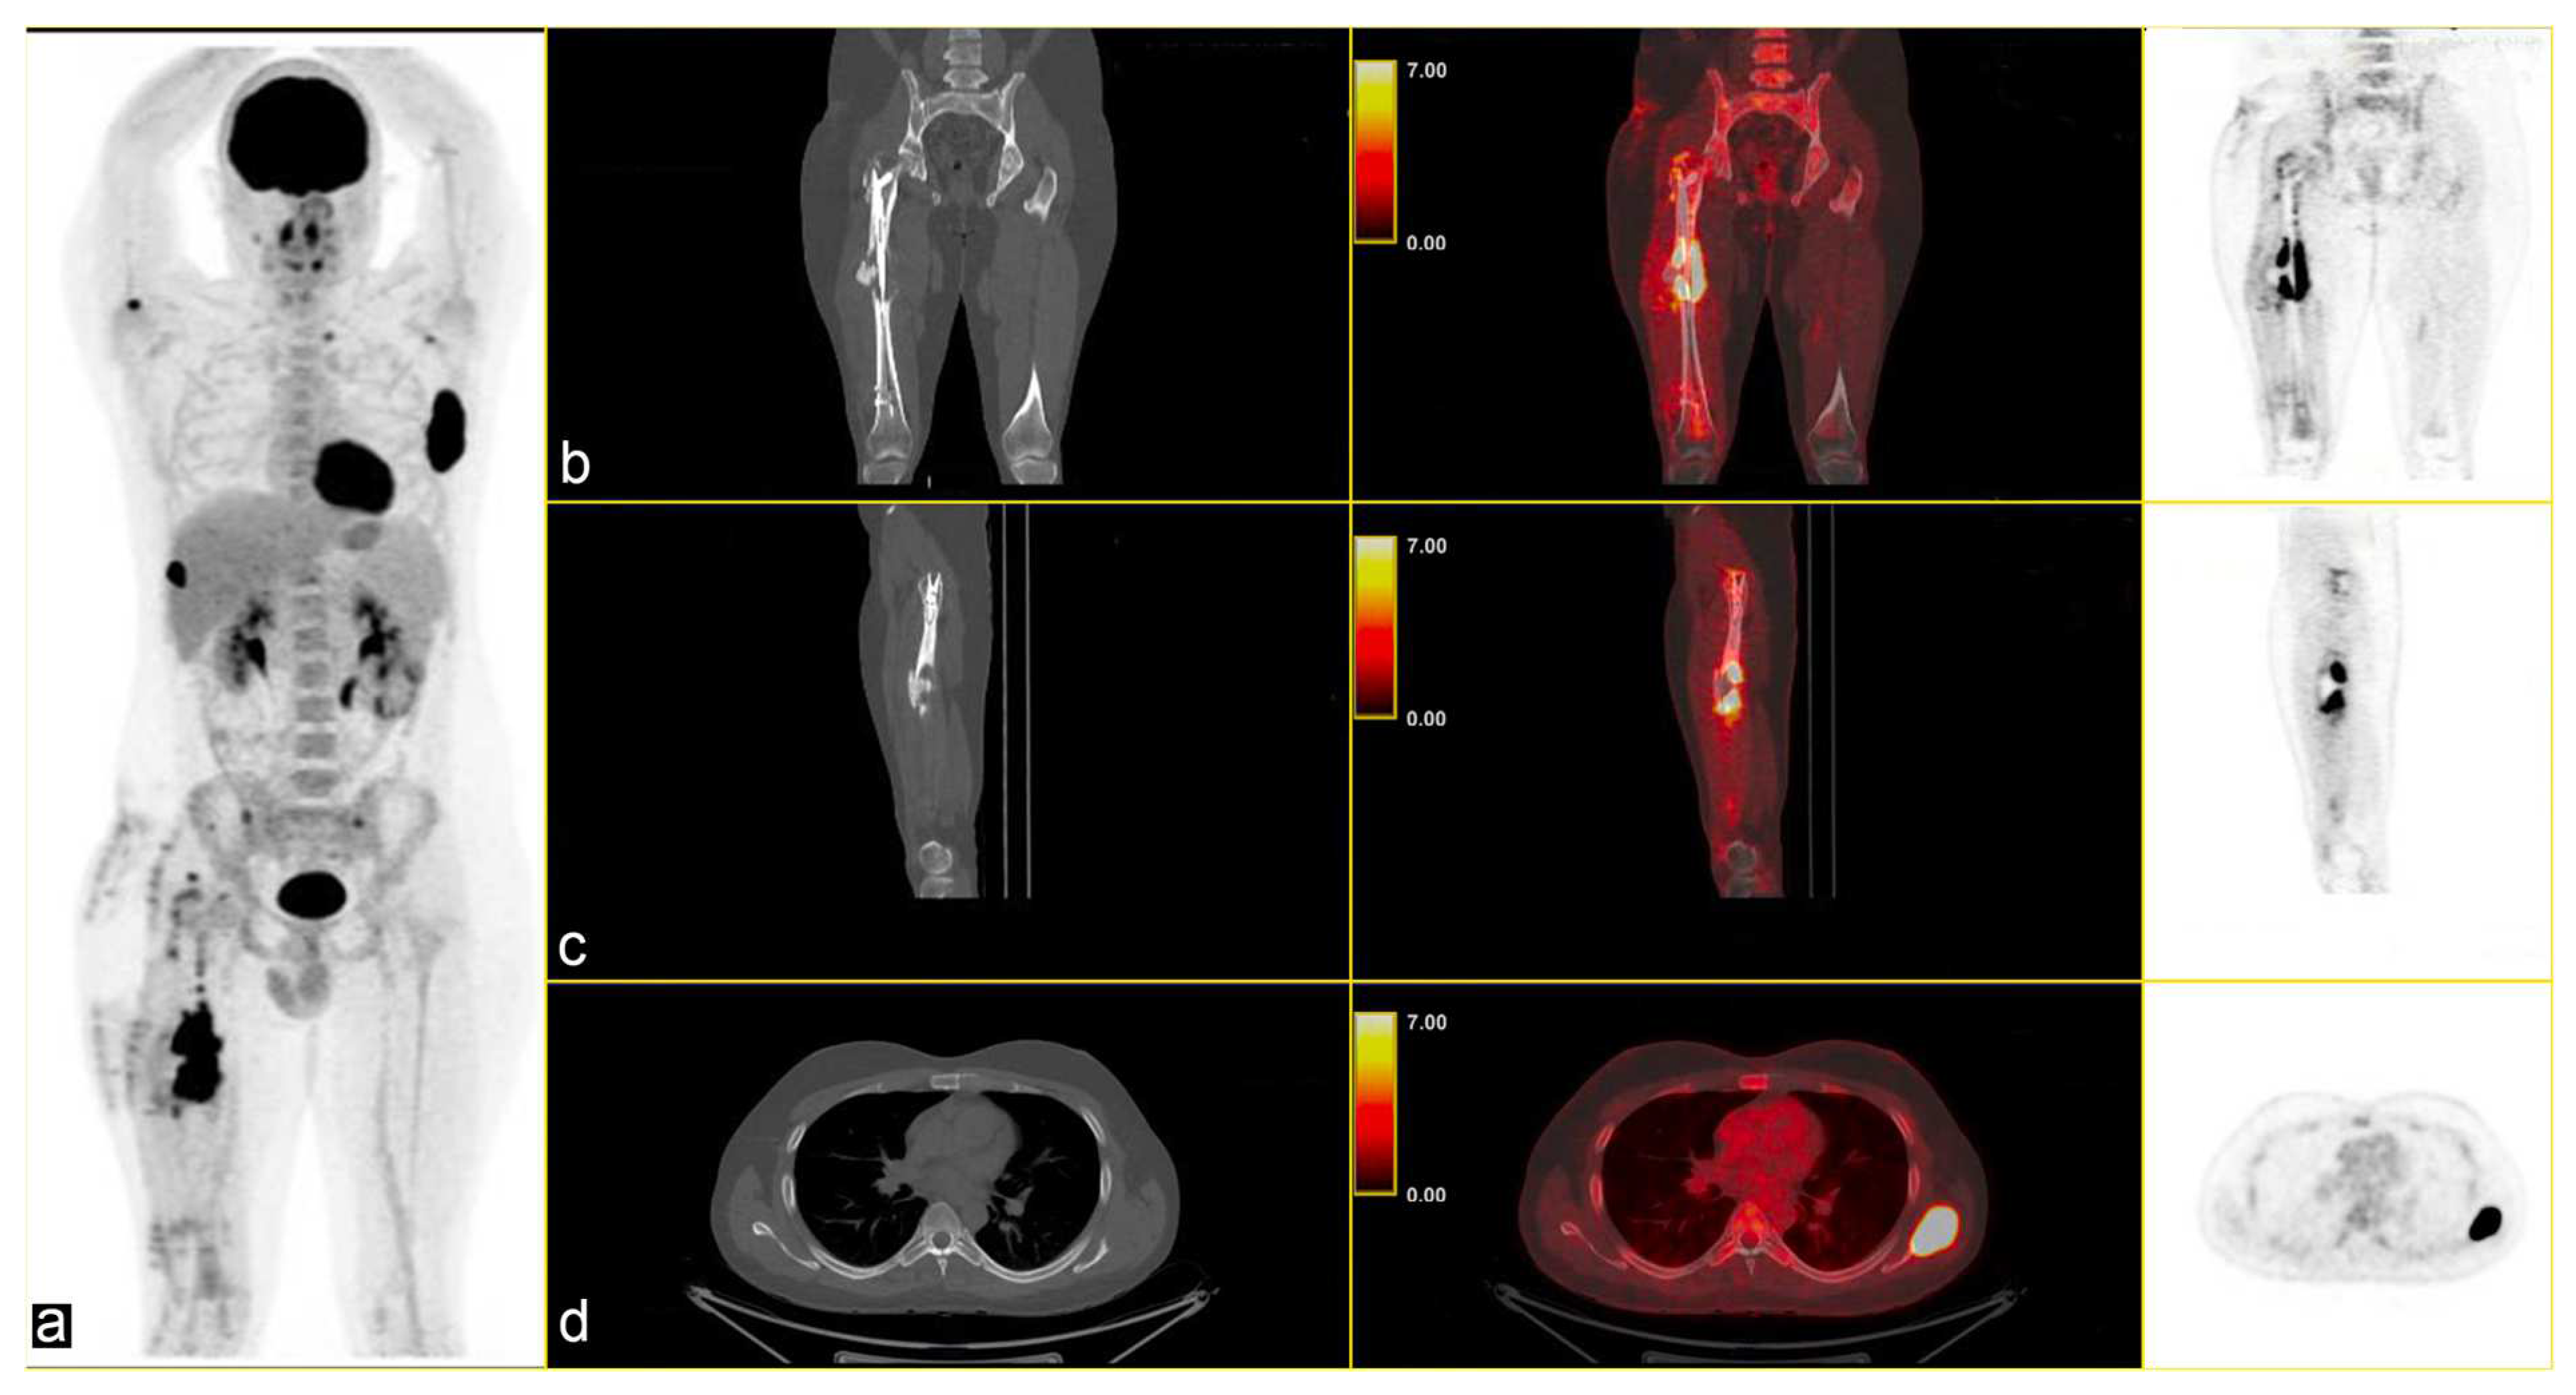

The multidisciplinary tumour committee recommended positron emission tomography (PET), which revealed multiple metabolically active lytic/sclerotic lesions in several bone sites: the right femur (SUVmax 22.5) at the level of the lateral margin of the left scapula (SUVmax 35), the glenoid cavity of the ipsilateral scapula (SUVmax max 6.7), the right humerus (SUVmax 10.1), in the lateral side of the right rib (SUVmax 22), in the left transverse process D1 (SUVmax 5.4), and in correspondence with the thoracic vertebrae T11 (SUVmax 5.4) [Figure 2].

Figure 2.

(a) Maximum Intensity Projection (MIP) shows several skeletal lesions at different sites; CT-PET fusion images: (b,c) sagittal images of the primary lesion in the left femur and (d) an osteolytic lesion (SUVmax 35) in the left scapula (b–d): CT on the left, CT fused images in the middle, and PET image on the right.